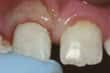

Dinte frontal fracturat

Dinte parţial fracturat: Dacă nu există durere şi fragmentul desprins este mic, puteţi decide singur dacă, cum şi când doriţi repararea lui. În funcţie de dimensiunea fragmentului desprins, dintele poate fi şlefuit sau corectat prin proceduri de cosmetică dentară. Alte opţiuni includ faţetarea, reconstituirea coronară şi obturaţia. Rugaţi medicul dentist să vă prezinte aceste soluţii. Dacă fractura s-a produs la suprafaţa unei obturaţii sau la un dinte artificial, se impune înlocuirea acestora.